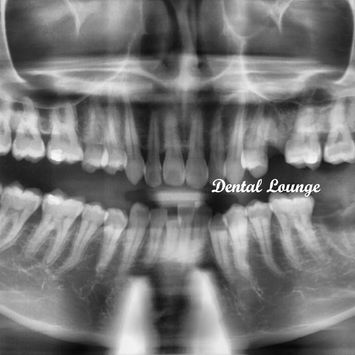

Post-operative Assessment

Post-operative CBCT taken.

No tooth remnants noted.

IDN and maxillary sinus intact and not involved in the surgery.